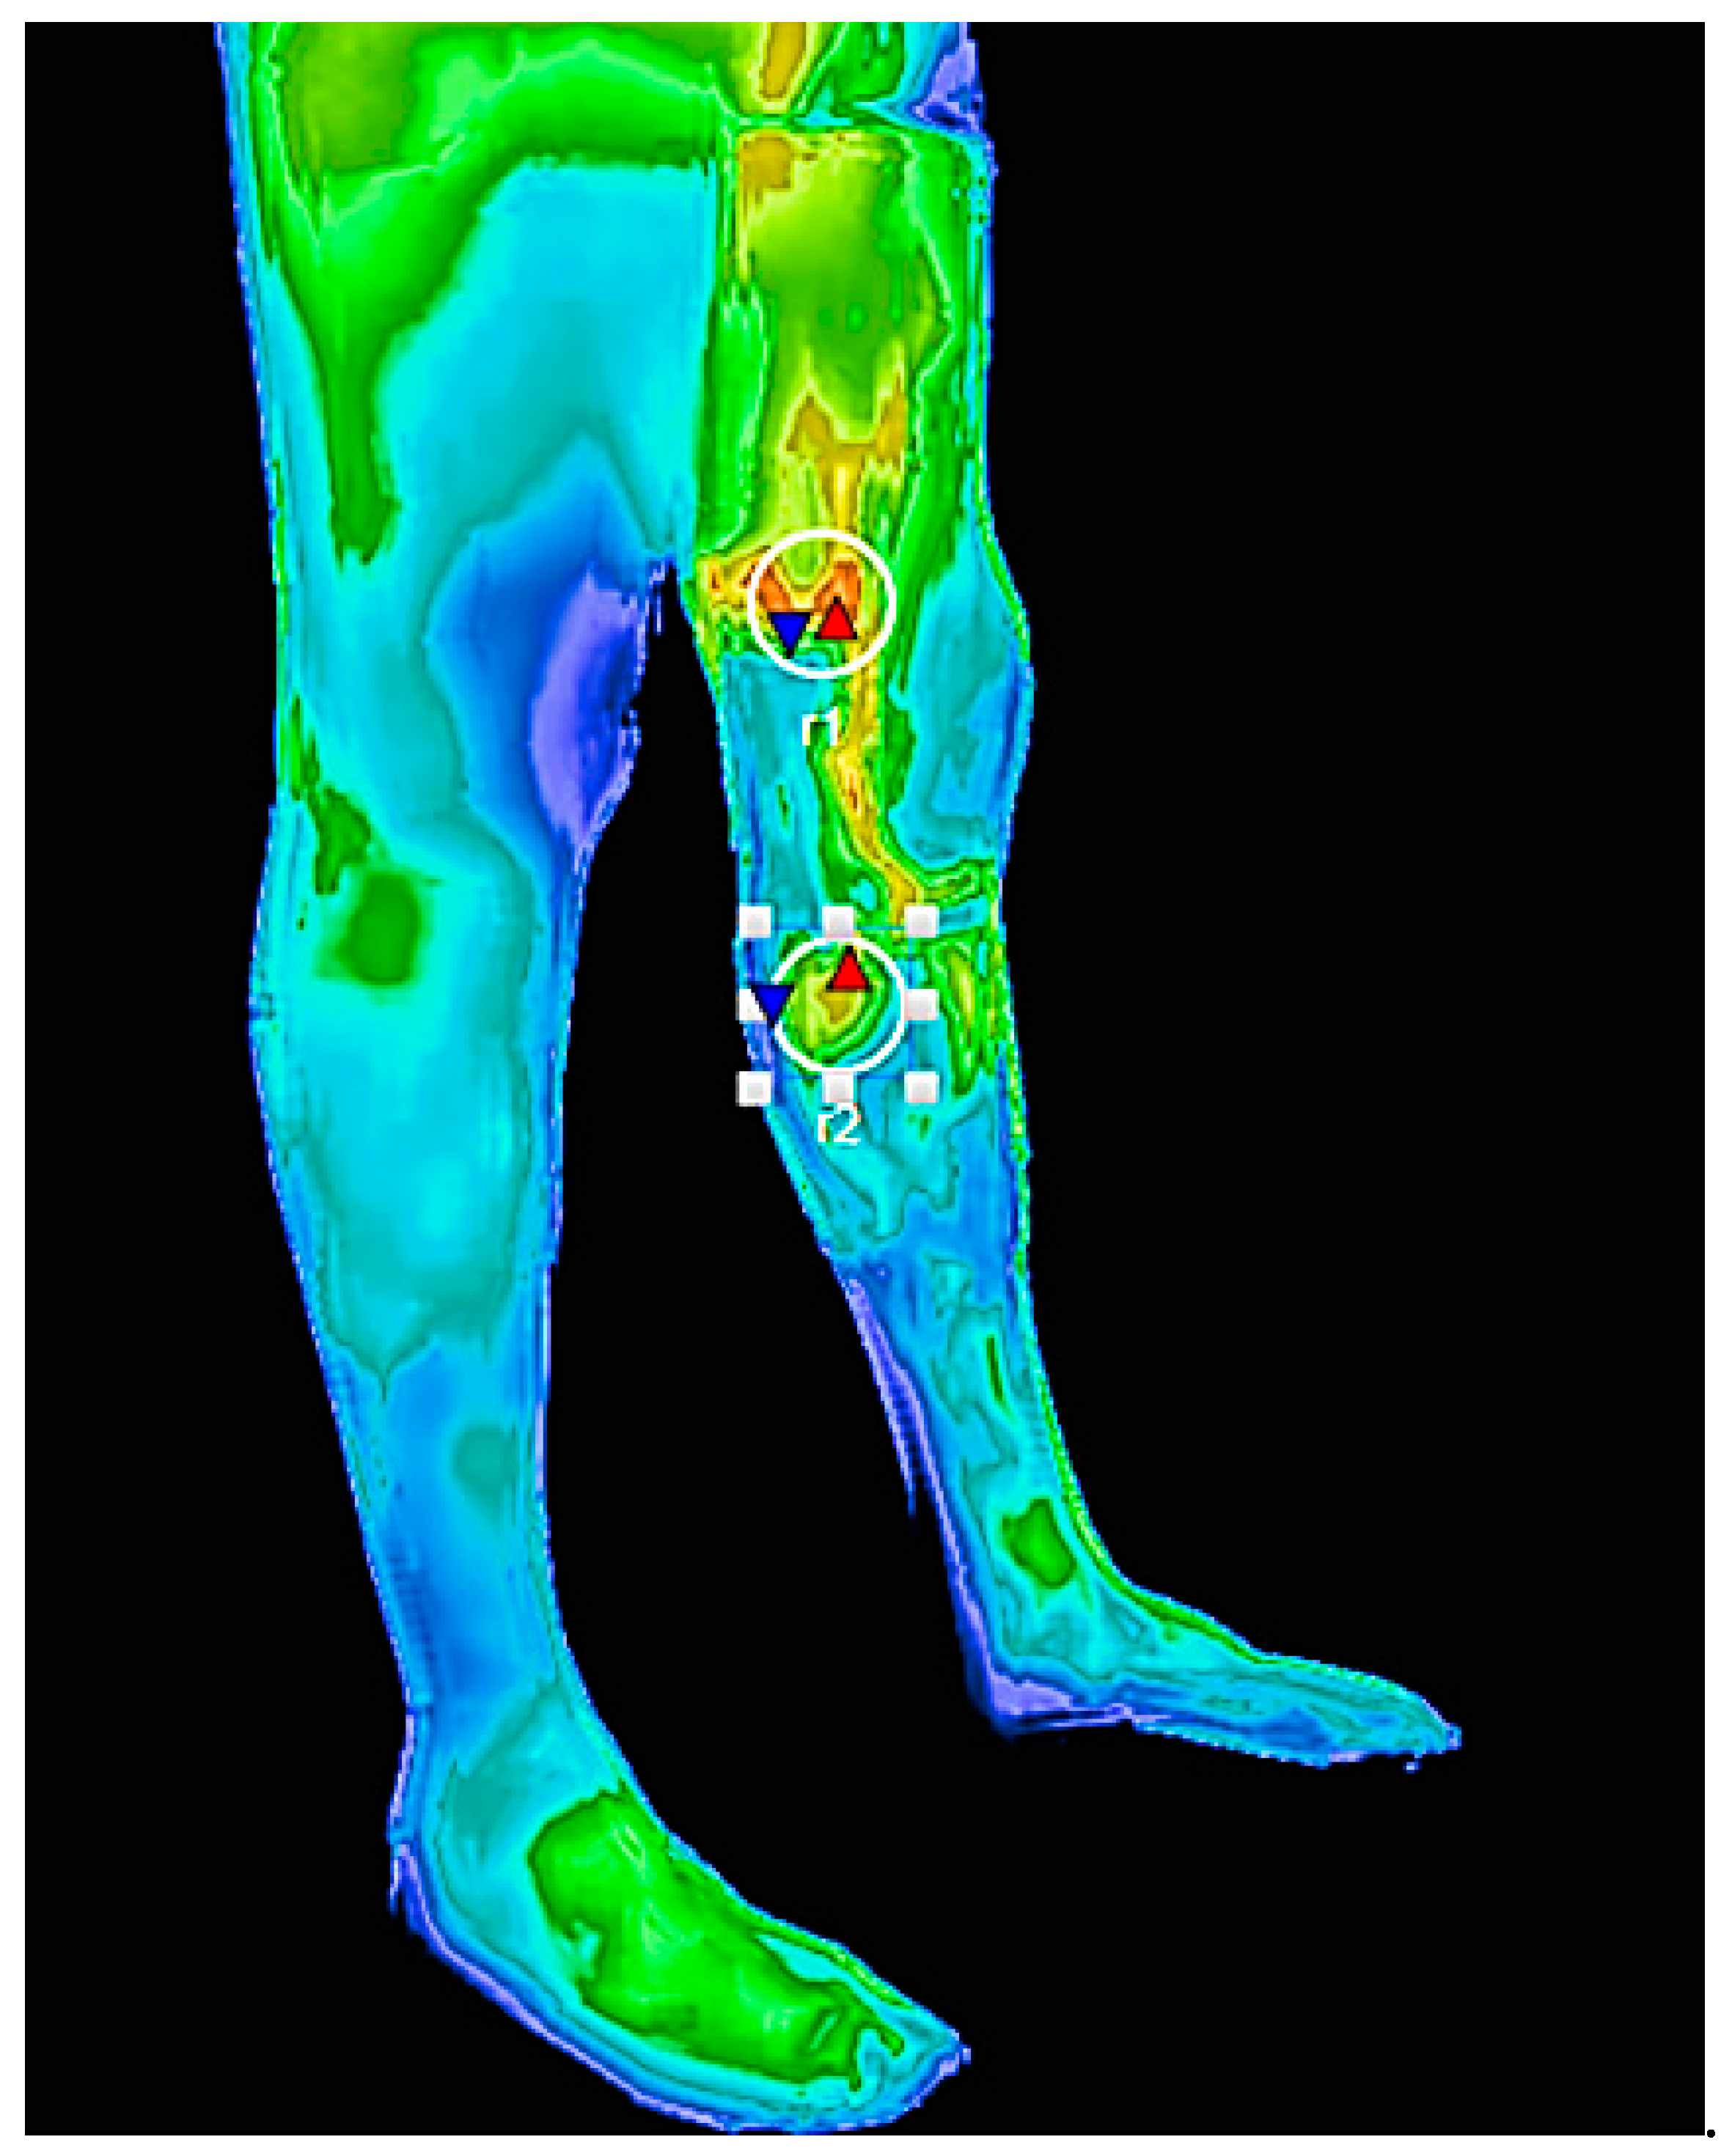

Can Dual Infrared–Visual Thermography Provide a More Reliable Diagnosis of Perforator Veins and Reflux Severity?

3. Results